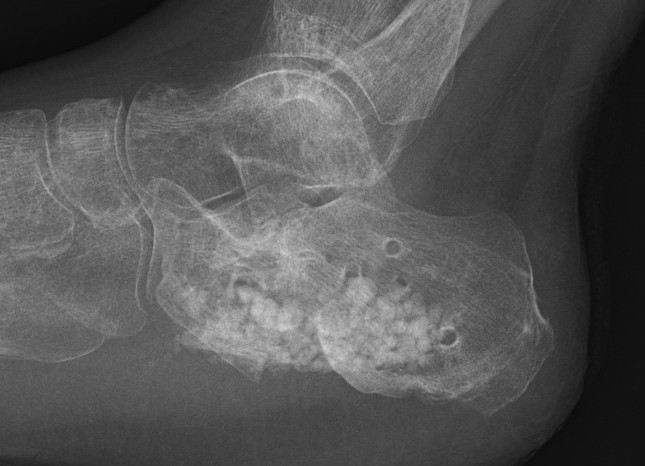

Calcaneal Malunion

Issues

Varus hindfoot - locks midfoot

Peroneal impingement

Shoewear problems

Options

Lateral wall exostectomy and peroneal tenolysis

Calcaneal osteotomy

STJ arthrodesis

Osteotomy for calcaneal malunion surgical technique PDF

Vumedi calcaneal osteotomy for malunion video

Results

Farouk et al Foot Ankle Int 2019

- 18 varus calcaneal malunions

- combined subtalar joint fusion / calcaneal osteotomy / lateral wall exostectomy

- outcome score increased from 60 to 80